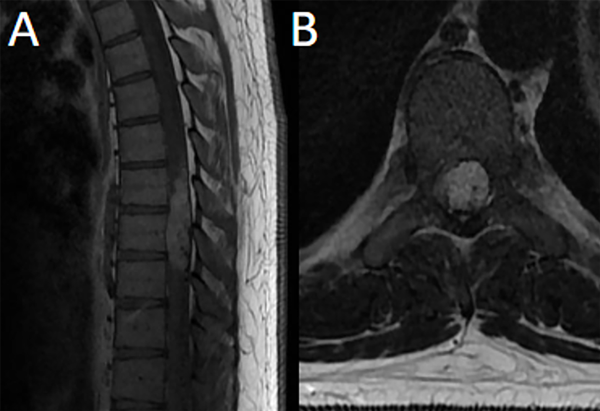

Fig 7. Caso 3. RM: T1 con contraste sagital (A) y axial (B) evidenciando lesión nodular intradural-extramedular altamente vascularizada con realce homogéneo post contraste de topografía T7-T9 que ocupa casi la totalidad del canal desplazando la médula con mielomalacia asociada.